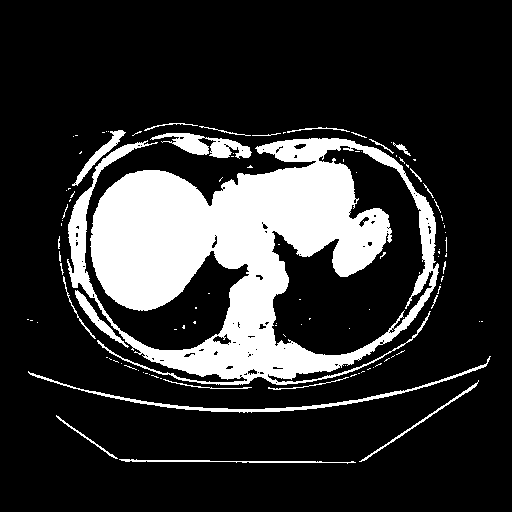

Generated VENOUS CT scan (A→B translation)

Full window (WL 1023.5, WW 4095 β†’ Low βˆ’1024, High +3071)

Actual HU range: [-1024.0, 3071.0]